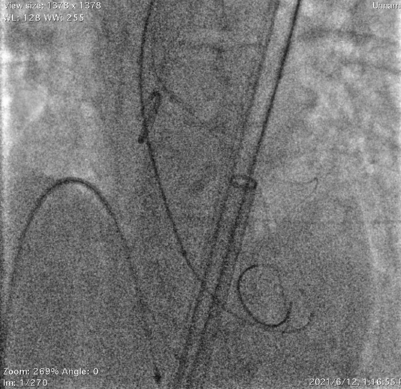

采用右冠guidezilla+预置支架保护,在右足Double-S体位下,选择Venus-A Valve 23瓣膜精准释放,跨瓣后及释放过程中患者持续低血压,释放2/3后血压仍无法恢复,调整好JR指引导管和guidezilla深度后,完全释放瓣膜。交换猪尾导管后复苏推药,患者血压逐渐恢复正常水平。

瓣膜释放后造影显示瓣膜定位准确,整个支架往右冠脉窦偏移,左冠显影正常,无遮挡。小心回撤guidezilla至冠脉口,JR指引导管内造影显示右冠脉遮挡仅留一条细线,决定植入烟囱支架,并充分后扩张。

术后心电图显示QRS波间期正常,生命体征平稳,跨瓣压差不大。